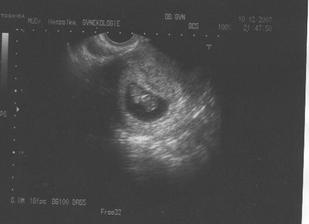

♥ 10.12.2007 - jsme 9t2d a miminku krásne bije srdíčko. Vše je v pořádku. A dostali jsme těhuprůkajdu!